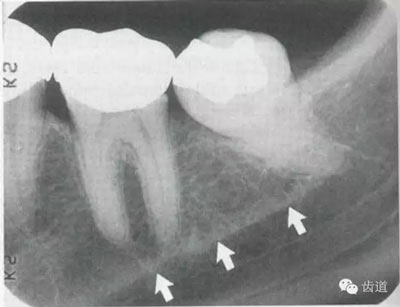

3)頦孔:

位于前磨牙根尖區(qū)域,為一大致圓形密度低的影像。頦孔位置變異大,多位于第二前磨牙根尖稍下,注意與根尖周病變區(qū)別,其要點是牙周膜及其骨硬板是否連續(xù)不斷。